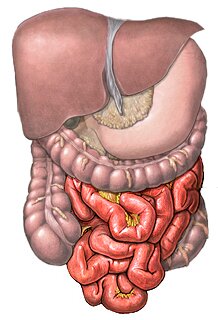

Синдром раздраженного кишечника (СРК) – заболевание, с которым пациенты редко идут к Далее...

Подходящая диета при заболеваниях ЖКТ – это хороший способ добиться улучшения самочув Далее...

Вздутие живота – неприятное явление, которое периодами беспокоит каждого. Основные си Далее...

Часто бывает так, что человек является носителем паразитарных организмов, даже не под Далее...

Заболевания органов ЖКТ, согласно статистике ВОЗ, молодеют год от года. Хронические г Далее...

Болезнь Крона представляет собой воспалительное заболевание кишечника, которое сопров Далее...

МРТ органов брюшной полости – современная процедура, основанная на применении ядерно Далее...

Болезнь Крона – это хроническое воспаление кишечника, которое впоследствии перерастае Далее...

Желчно-каменная болезнь – это образование камней в желчном пузыре и желчевыводящих пр Далее...

Метеоризм или вздутие кишечника давно обозначено врачами не как отдельное заболевание Далее...

Печень представляет собой мини-лабораторию организма человека. В этом органе происход Далее...

Что такое боль, известно абсолютно всем. Боли в животе бывают особенно мучительными, Далее...

Каждому второму жителю нашей страны знакомо неприятное чувство жжения в области груди Далее...

Неспецифический язвенный колит (НЯК) представляет на сегодняшний день острую проблему Далее...